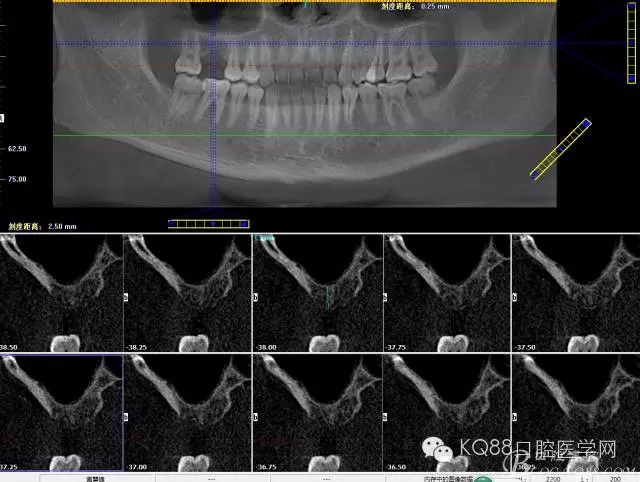

下面是拔牙后三個月的CBCT。垂直骨高度約6.7mm。

另外一個切面。垂直骨高度不夠,準(zhǔn)備 :做內(nèi)提升,植骨,植入植體。

植入后,CBCT

另外一個切面。竇底粘膜完整連續(xù)。可以看到上下咬合的位置關(guān)系。

下面兩張是種植前后的對比片子。

手術(shù)前

手術(shù)后。